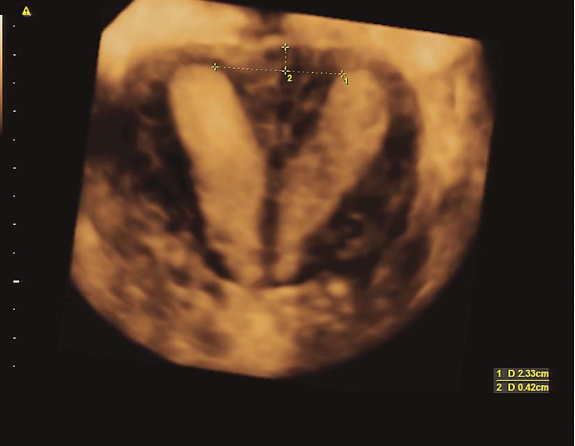

双角子宫三维超声

双角子宫二维超声碘油造影

完全纵隔子宫三维超声

不完全纵隔子宫三维超声